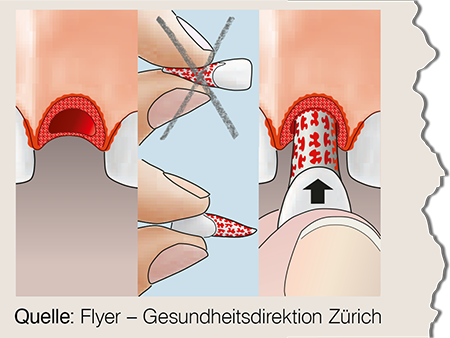

Zahn ist herausgeschlagen

Wenn möglich sofort wieder einsetzen!

Sonst sofortiger Transport zum Zahnarzt!

Behandlung innert Stunden nötig!

Bewahren Sie den ausgeschlagenen Zahn in einer Zahnrettungsbox auf (...erhältlich bei Ihrer Apotheke oder bei einer Notapotheke).

Alternativ eignet sich kühle H-Milch oder wickeln Sie den Zahn mit etwas Speichel vom Patienten in einer Frischhaltefolie oder in ein Plastiksäcklein.

Suchen Sie sofort Ihren Zahnarzt auf und bringen Sie den ausgeschlagenen Zahn mit.

Wichtig:

- Zahn nicht an der Wurzel anfassen!

- Niemals den Zahn reinigen oder trocknen!

- Bei sichtbarer Verschmutzung nur kurz unter fliessendem Wasser abspülen.

- Zahn nicht mechanisch reinigen oder desinfizieren!

- Zum transportieren Zahn feucht aufbewahren!

Nicht geeignet sind:

- Desinfektionsmittel wie Alkohol etc.